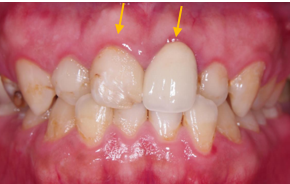

- 前牙顏色不均+長時間錯咬導致門牙切端形狀不一。 做前牙貼片覆蓋,一口乾淨帥氣的白牙就出現啦!!!

- 前牙原錯咬,上排牙齦高低不一,做〖 牙冠增長術 〗 修飾牙齒形狀。

治療後 :牙冠增長術修整牙齦+貼片覆蓋,修飾牙齒形狀及顏色,

笑齦改善,閃亮亮的白牙出現啦。